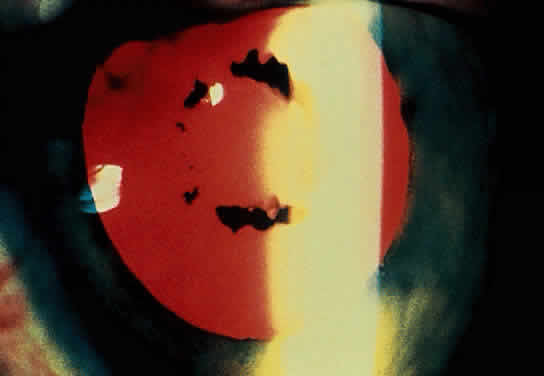

The conjunctivitis is usually described as mucopurulent and may be sterile. It may be accompanied by an iridocyclitis, episcleritis, or scleritis. Punctate and subepithelial corneal involvement has been reported. The iridocyclitis may be the presenting ocular manifestation. Recurrences are usually associated with an acute iridocyclitis, which is of rapid onset with conjunctival and episcleral edema and injection. The corneal endothelium has cellular debris and poorly defined, small-sized to medium-sized keratic precipitates.30 Heavy flare and cells and a very early tendency toward formation of posterior synechiae is characteristic, more so than in most other forms of acute iridocyclitis (Figs. 1, 2, and 3). Even the most aggressive pupil dilation management is sometimes inadequate for preventing synechiae. A peripheral iridectomy may be necessary to prevent iris bombé and angle closure if the synechiae cannot be broken enough to establish an opening for aqueous through the pupil (Fig. 4). The heavy flare is sometimes so plasmoid that cells are immobile and a fibrinlike clot may be seen in the pupil opening as the inflammation resolves. Cells and inflammatory debris may be seen in the vitreous, and blurring of the disc margins and macular edema may occur with severe or prolonged episodes. Lens clouding and posterior subcapsular cataracts occur with prolonged or repeated episodes. Hypotony can occur after a severe or prolonged course and may persist after resolution. Occasionally, secondary glaucoma may occur, owing to the anterior chamber reaction, in which case it will resolve as the inflammation resolves. With repeated recurrences, damage to the trabecular meshwork may occur, and prolonged recalcitrant glaucoma may result that may be poorly responsive to any medical or surgical management. This can be a serious factor in permanent visual loss with this type of iridocyclitis.15,16,30,31

Fig. 1. Early onset complete posterior synechiae in iridocyclitis with Reiter's disease.

Fig. 2. Partial dilation of pupil in Figure 1.

Fig. 3. Completed dilation of pupil in Figure 1 with pigment on anterior surface of the lens.